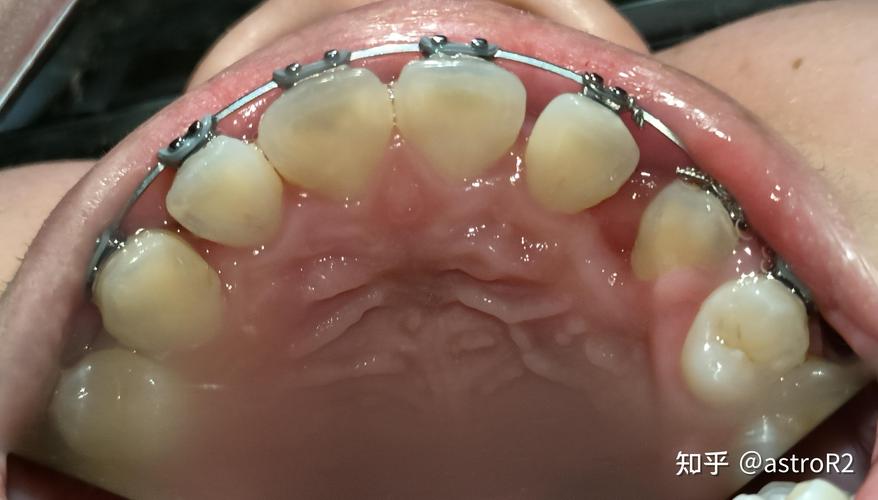

(图片来源网络,侵删)- 作为“国际医院”,其硬件设施(诊室环境、消毒流程、等候区等)通常会比普通公立医院更新、更舒适、更注重隐私保护。